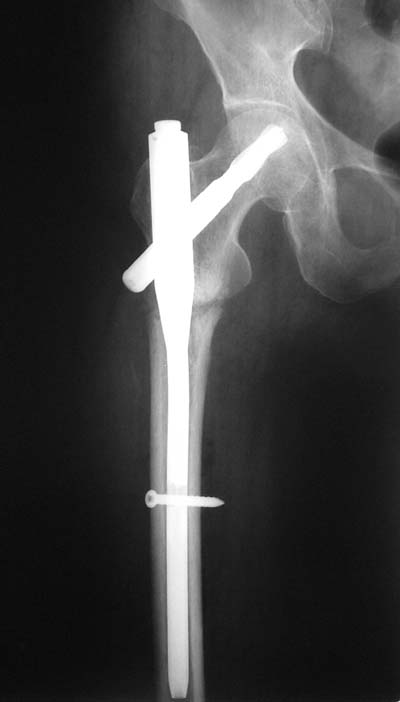

Не думаю так. см вложение.

> Не думаю так. см вложение.

Для такого перелома вполне может быть использован диафизарный штифт, который отечественного производства я даже боюсь считать во сколько раз дешевле... Недавно несколько примеров я закидывал.